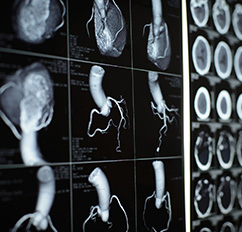

Die vorläufige Befundbesprechung mit einem Arzt erfolgt in der Regel etwa 20 Minuten nach der Untersuchung. Sollten Sie einen Betablocker erhalten haben, bitten wir Sie, noch weitere 15 Minuten bei uns zu bleiben. Ihr Arzt erhält einen schriftlichen Befund innerhalb weniger Tage. Die abschließende Befunderstellung erfolgt unter Verwendung einer aufwendigen Nachbearbeitungssoftware, sodass die abschließende Bewertung der Untersuchung nicht unmittelbar nach der Untersuchung erfolgt, aber innerhalb eines Zeitraumes von wenigen Tagen.